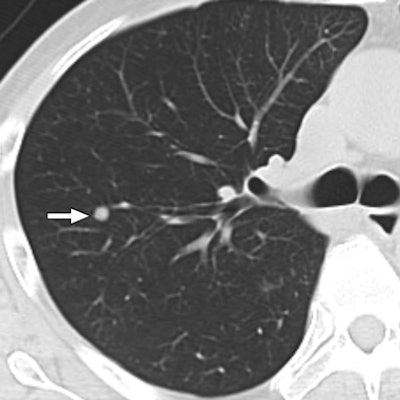

| 47-year-old man with metastatic hepatocellular carcinoma. Above, axial CT scan obtained before tomotherapy shows small well-defined nodule (arrow), target lesion, in right upper lobe. Below, three-month follow-up CT scan reveals focal area of ground-glass attenuation (arrows) around target, representing radiation pneumonitis. All images courtesy of the American College of Radiology. |